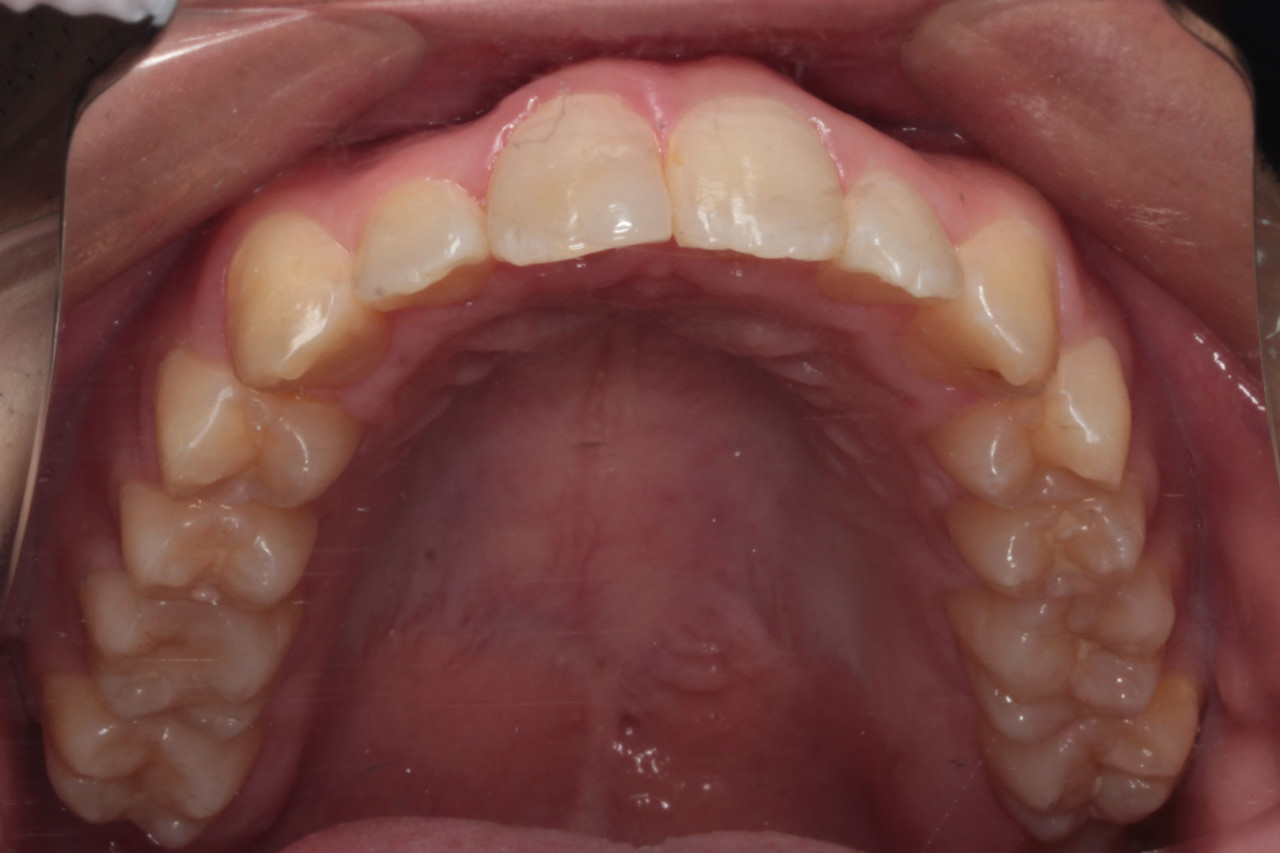

上顎 治療前

上顎 治療後

今回の症例は写真のように上の中心から2番目の歯が左右とも奥に入り込んでいてかなりスペースのない状態でした